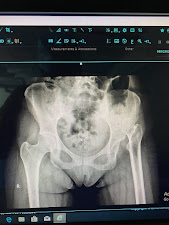

3 month wt bearing xray showed a corrected LLD